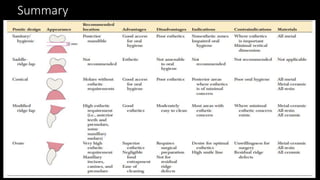

The document discusses pontic design for fixed dental prostheses. It covers pretreatment assessment of residual ridge contours, classifications of ridge deformities, surgical modification techniques, and ideal requirements for pontics. Pontic designs are classified based on their shape and materials. Factors in pontic selection include esthetics and oral hygiene. Common designs for anterior and posterior regions are described, including sanitary, ovate, and saddle pontics. Biological considerations for pontic design involve maintaining the residual ridge, abutment teeth, and supporting tissues.